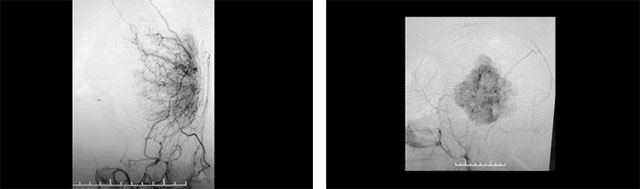

▲ 肿瘤病灶血供丰富

沈建康教授团队首先为患者进一步完善检查,头颅MRI增强检查显示,患者左侧颞顶叶部位的肿瘤约为6.3cm×4.4cm×6.7cm,体积巨大。经行DSA检查发现,肿瘤包裹缠绕多根重要的动脉血管,血供非常丰富。尽管切除难度高,手术风险大,但综合分析考虑肿瘤为脑膜瘤,系良性肿瘤,手术成功可以治疗好。

围绕这一棘手情况,沈教授团队联合医院脑血管病科主任张琪博士,开展了严谨的评估讨论,以确定治疗方案。临床经验丰富的沈建康教授指出,颞顶叶部位巨大脑膜瘤,治疗方法为手术切除,患者手术指征明确,未见明显手术禁忌。由于该肿瘤有明显的颈外动脉供血,讨论后考虑采取“术前栓塞+肿瘤切除”的手术方案,以减少术中出血,利于肿瘤分块切除,尽可能避免意外发生。

两台手术接力 成功切除巨大脑瘤

术前,沈教授团队向胡女士家属充分沟通、明确手术的必要性和风险性,并获得充分理解、签字同意后开始手术。借助先进的双C臂FD20/20双向血管造影系统DSA,先由张琪博士为患者行经导管颈外动脉供血血管栓塞术,脑血管造影显示,患者肿瘤供血动脉主要由左侧脑膜中动脉、颞浅动脉及左侧大脑后动脉脑膜支参与。张琪博士在DSA引导下分步完善栓塞供血动脉,直至完全切断肿瘤的主要供血,为沈建康教授进行肿瘤切除创造了有利条件。